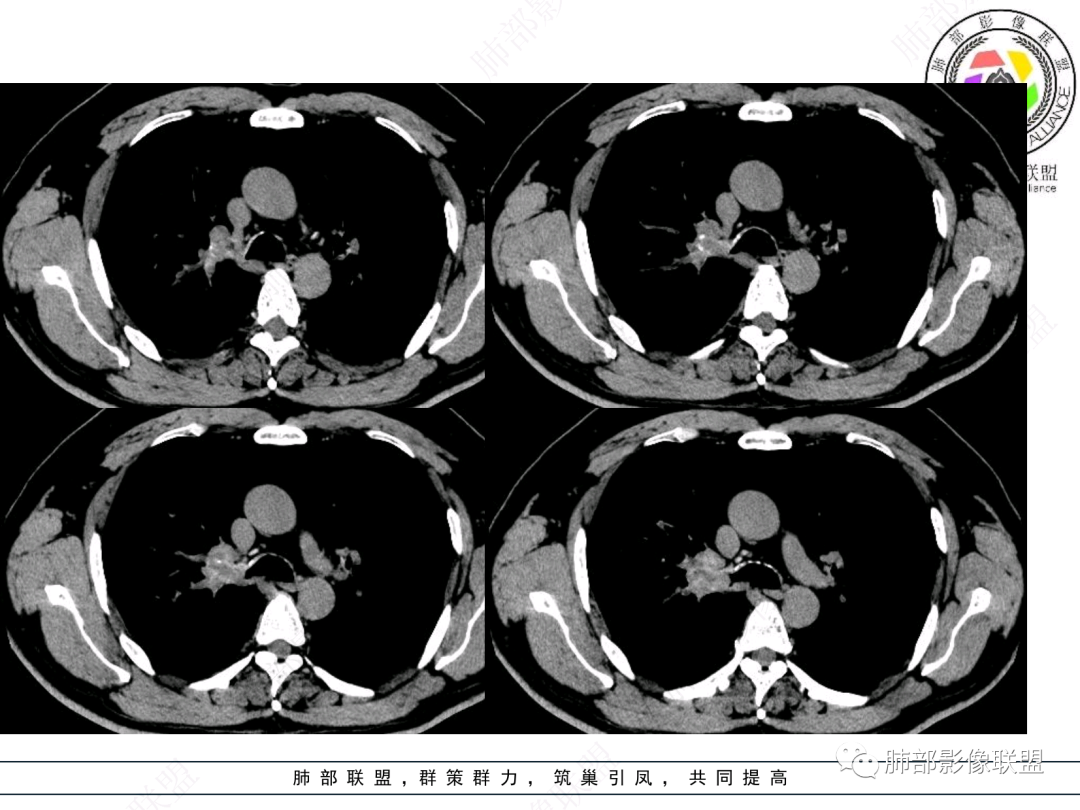

屈运良:

右上叶支气管闭塞,腔内可见软组织肿块,右肺门见肿大淋巴结,远端有阻塞性肺炎,右肺门肿块不均匀强化,其内血管侵蚀边缘模糊,定性恶性,考虑鳞癌或腺样囊腺癌

毛勤香:

赶个尾巴,肺门区肿块,气管闭塞,壁增厚,局部破坏,远端阻塞性炎症,中度强化,肺气肿背景,定性恶性,常规鳞癌

这个病例比较好,我们的观察点在哪?这是右上叶支气管病变,需要了解:腔内、壁、腔外、远端,腔内有软组织密度影,近端膨隆。

如果在这种情况下临床想通过CT了解啥?主要是:a、与附近结构的关系:血管、淋巴结;b、远端情况;c、其他区域转移情况;

影像上分析的观察点:腔内、壁、腔外、远端,然后就是远端肺组织、淋巴结、肺血管、胸膜、其他肺部,这个人就是阻塞性炎症为主。